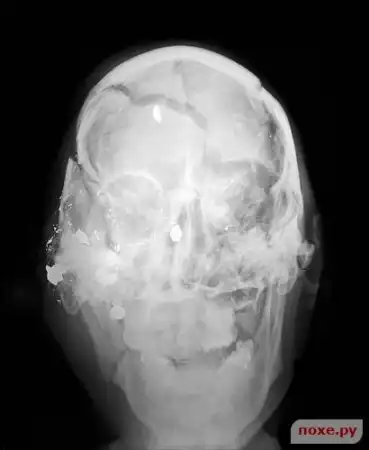

Выстрел в голову.